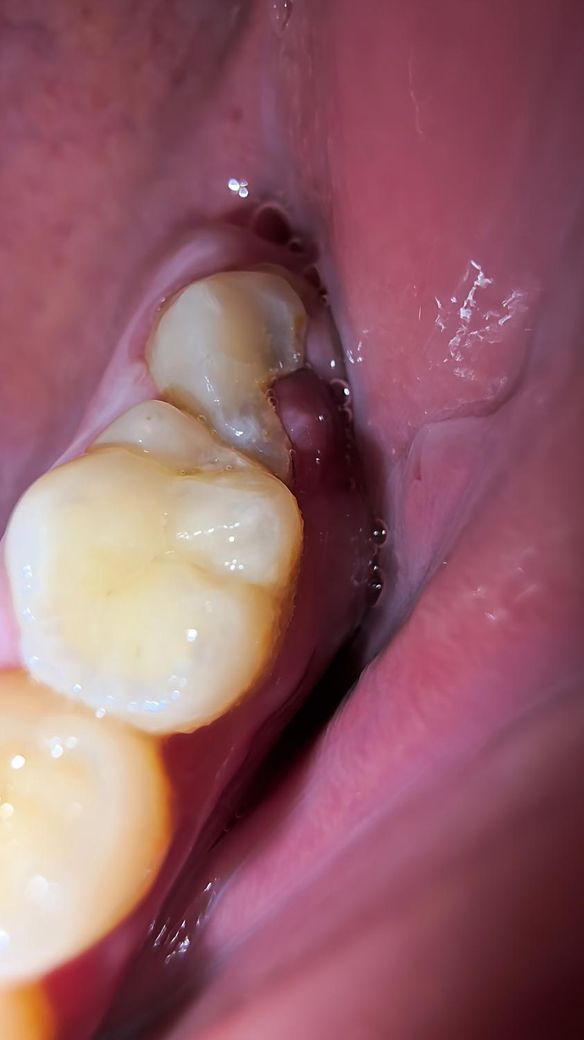

군대에서 충치가 있다고 확인한답시고 절반을 삭제시키고 무조건 발치를 해야된다고 했습니다 그러고나서 방치를 해왔는데 발치가 답일까요? 그리고 저기 가운데는 잇몸이 차오른건가요?

사진상으로도 충치가 많이 진행된 상태고 잇몸도 많이 증식된 상채라 발치를 해야될 가능성이 높아 보입니다.

충치가 심하네요 아마 치수(치아 속 신경)까지 노출된 것 같고 붉은 덩어리는 노출된 치수가 자극받아 생긴 치수용종(pulp polyp) 같습니다 발치 혹은 신경치료 후 후처치를 시도해볼 수 있습니다